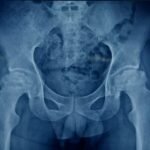

Total Hip Replacement

You may be a candidate for hip replacement surgery if you have hip arthritis which is refractory to conservative treatment.